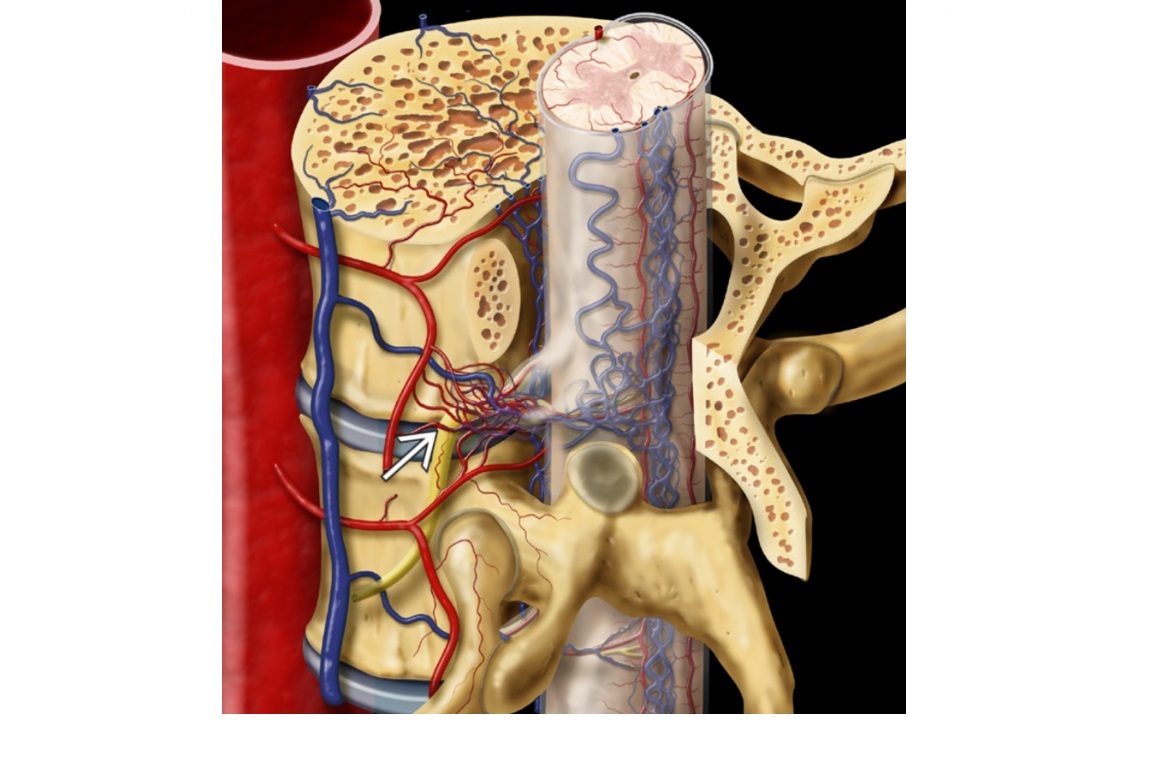

Elderly with progressive radiculomyelopathy. MRI - Abnormally enlarged, T2-hyperintense distal cord covered with dilated pial vein flow voids?

A

Type 1 Dural AVF

Most common type

Between the radiculomedullary arteries and veins